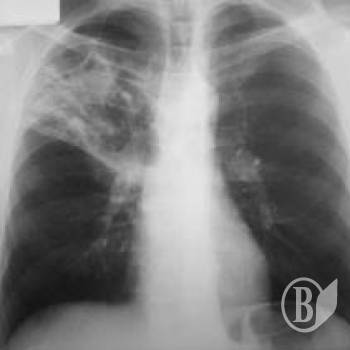

Найбільш розповсюдженими у 2012 році були хвороби органів дихання.

Захворюваність на них становила 33,3 тис. випадків на 100 тис. населення.

А також травми, отруєння та деякі інші наслідки дії зовнішніх причин – 5,4 тис.; хвороби системи кровообігу – 4,5 тис.; шкіри та підшкірної клітковини – 4,1 тис.; сечостатевої системи, ока та його придаткового апарату – 3,6 тис. випадків по кожному класу захворювань; кістково-м’язової системи та сполучної тканини – 3,4 тис.

Захворюваність серед жінок вища, ніж серед чоловіків. У 2012р. вона становила 70,7 тис. випадків на 100 тис. жінок, у той час, як із 100 тис. чоловіків хворіли 67,9 тис.

За даними Обласного центру інформаційно-аналітичних технологій та пропаганди здорового способу життя, у 2012р. в медичних закладах області, що підпорядковані Міністерству охорони здоров’я України, зареєстровано 745,7 тис. випадків захворювань з уперше в житті встановленим діагнозом, або 69,4 тис. випадків у розрахунку на 100 тис. населення (у 2011р. – 70,2 тис.).